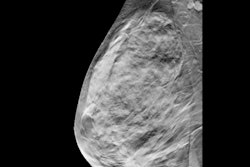

The study, led by Caezar Jara of Adventist Health and Rideout, evaluated the impact of the Viz.ai platform combined with standardized transfer protocols and a partnership with a comprehensive stroke center. Performance gains included an 84% reduction in time from CT angiography completion to LVO detection, and a reduction in care-team notification time from 45 minutes to seven minutes, according to the study. The 113-minute average door-in-door-out time exceeded the Joint Commission's 120-minute national benchmark.